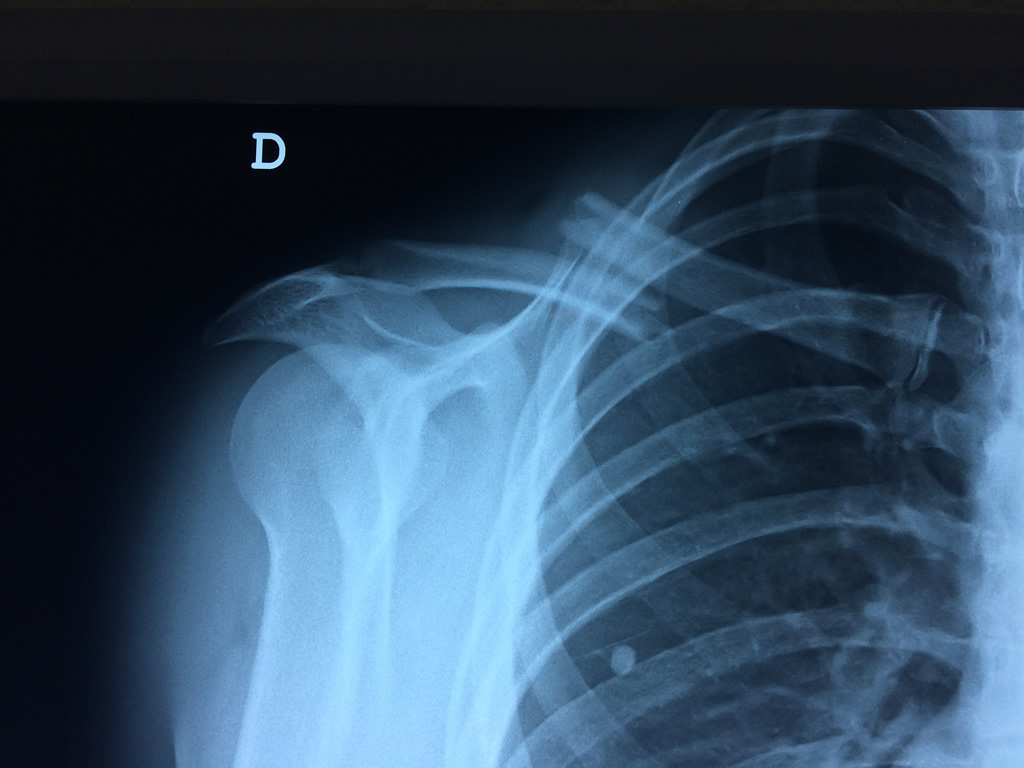

Cirugía de Fémur - Clavícula

La clavícula es un hueso largo, con forma de "S" itálica, situado en la parte anterosuperior del tórax. Junto con la escápula forman la cintura escapular. Se puede palpar por toda su longitud y se extiende del esternón al acromion de la escápula, siguiendo una dirección oblicua lateral y posterior.